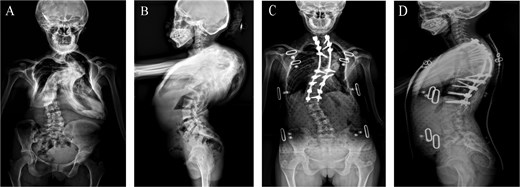

Significant differences were observed between the two groups in terms of hemoglobin levels at 24 h postoperatively (11.32 ± 1.46 vs. 10.06 ± 1.18 g/dL), prothrombintime values at 24 h postoperatively (11.45 ± 0.99 vs. 13.27 ± 1.38 s), and partial thromboplastin time (APTT) values at 24 h postoperatively (30.79 ± 4.51 vs. 35.69 ± 7.33 s), all showing statistical significance (P < 0.05). See Table 2 for details. A typical case of severe spinal deformity correction surgery is illustrated in Fig. 1.

A patient with severe spinal deformity undergoes corrective spinal surgery. (A, B) Preoperative anteroposterior and lateral X-rays showing severe spinal deformity (cobb angle ≥60°). (C, D) Postoperative anteroposterior and lateral X-rays at 1 month showing stable internal fixation with satisfactory positioning.